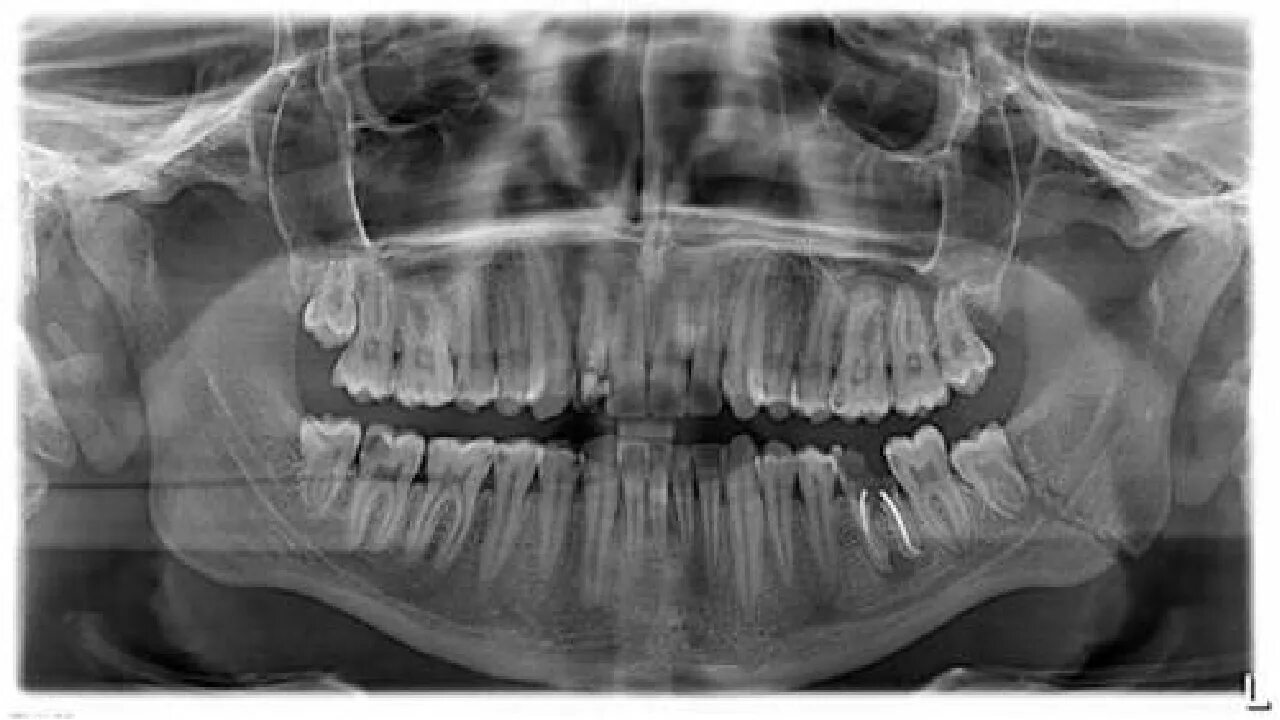

Снимок верхней и нижней челюсти